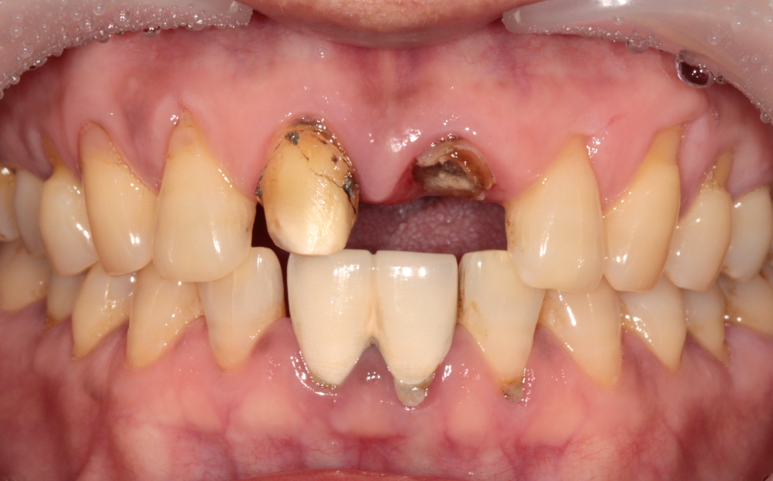

앞니 보철물이 빠져서 내원하시게 되신 환자분의 케이스입니다.

타원에서 치료받으신 보철물을 그동안 잘 사용하고 있었는데,

어제 갑자기 윗니 쪽으로 가벼운 충격이 있었고,

바로 보철물이 빠지셨다고 합니다.

2024. 1 기존의 보철물은 위 앞니 두 개를 연결한 형태였다고 하시네요.

환자분의 현재 상태를 보고 원인을 유추해 보았습니다.

기존에 연결된 앞니 보철물과 치아의 경계부 사이로 2차 충치가 진행이 오랜 기간 지속되었고,

보철물 내부의 치아에 충치가 심해져 약해져 있던 상태에서

작은 충격에 그 보철물이 빠져버리게 된 것입니다.

보철물 경계부에 생기는 2차 우식

(좌측: 다른 환자분의 케이스)

(우측: 이번 케이스 환자분의 아래 치아)